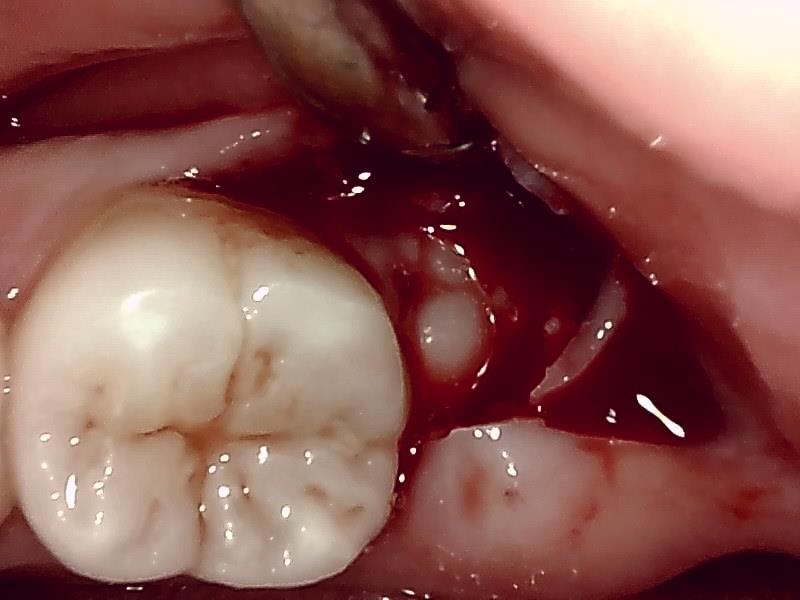

切開

歯牙分割

歯肉を切開し、歯が見えるようにして、

周辺の骨を削らないように親知らずを分割し抜きやすくしていきます。

当院では、傷口は最小限に、骨は極力削らずに行います。

骨が歯を覆っているケース以外は骨を削ることはありません。

親知らずのみにアプローチし歯を分割し最小限の傷口で取り出します。